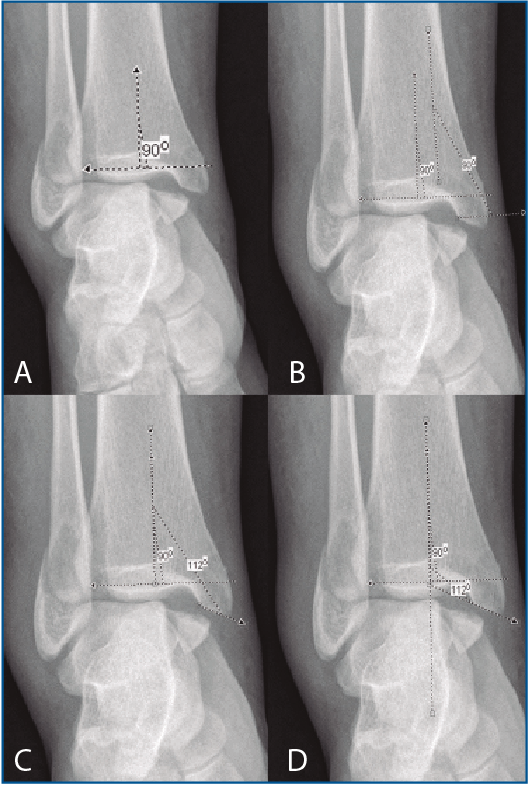

De cada uno, se han obtenido las siguientes mediciones radiológicas: tipo de lesión según Lauge-Hansen, número de maléolos afectados, medida del ángulo talocrural, ratio tibiofibular anteroposterior (AP), presencia o ausencia de superposición de colículos del maléolo interno con el peroneo, ECTF, solapamiento tibiofibular, ángulo de inclinación astragalina, línea de Shenton continua o discontinua, espacio claro medial y ángulo principal a estudio, el ángulo crurofocal medial (ACFM). Para analizar el ángulo principal, se debe obtener una línea perpendicular a la superficie articular tibial (del mismo modo que para el primer paso de la medición del ángulo talocrural); una vez hecho esto, se traza una línea entre el punto más medial y más lateral del trazo de fractura del maléolo interno en el origen tibial. El ACFM es el formado por esta línea y la perpendicular a la superficie articular tibial, y estará comprendido en un arco de valores posibles entre 0 y 180° (Figuras 1 y 2).

Figura 2. A: obtención de una perpendicular a la superficie articular; B: superposición de un brazo del ángulo a la perpendicular; C: situación del otro brazo en la línea formada entre los orígenes tibiales; D: medición completada.